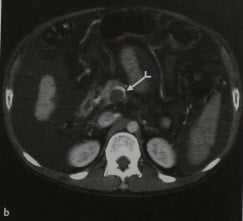

Тромбоз воротной вены. КТ после введения контрастного вещества. Идентифицируются острый тромб в воротной вене (а, стрелка), признаки распространения тромбоза на верхнюю брыжеечную вену (b, раздвоенная стрелка). Цирроз печени, спленомегалия, асцит, варикозное расширение вен пищевода (с).